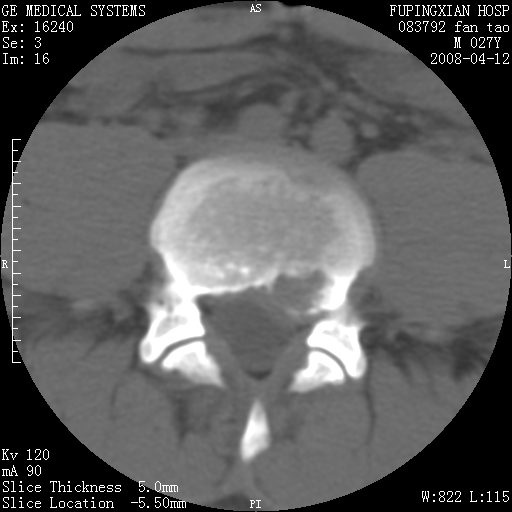

以下是引用前行在2008-4-13 13:53:00的发言:[br]椎间盘髓核终板下突出形成许莫氏结节及椎间盘突出,建议mr检查

以下是引用xclzq_910在2008-4-13 12:43:00的发言:[br]这个应该没什么了,椎间盘突出后反应性骨质吸收硬化.建议mr